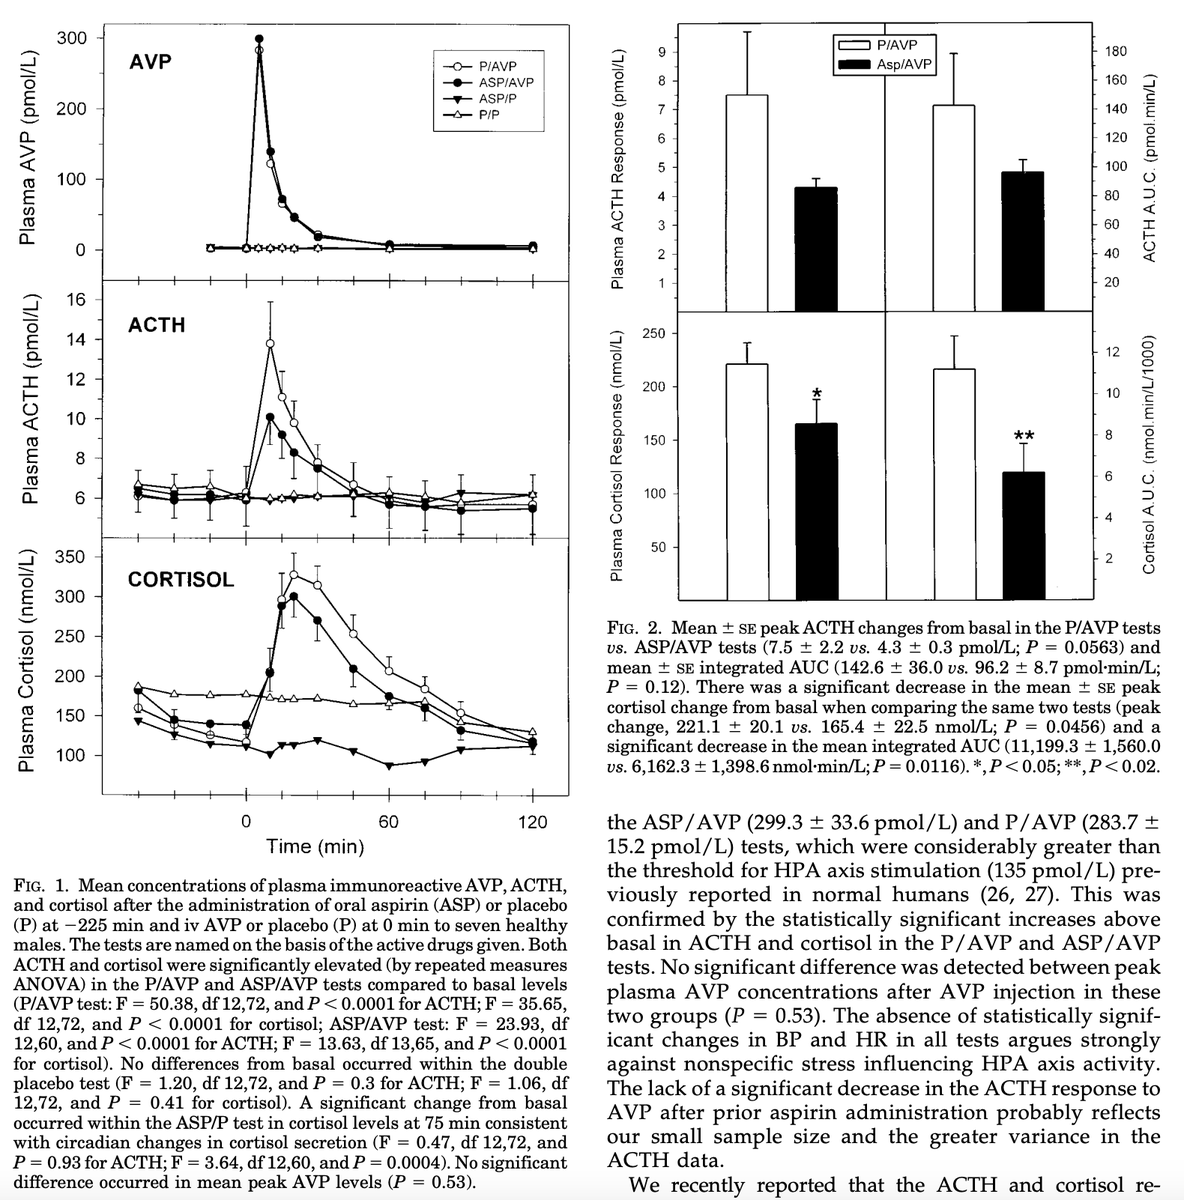

One of the KEY benefits of aspirin is its ANTI STRESS properties.

Many people report calmness and better sleep on aspirin, and this is likely a prime reason why.

Aspirin can actually lower the output of cortisol, our primary stress hormone, at baseline.

Many people report calmness and better sleep on aspirin, and this is likely a prime reason why.

Aspirin can actually lower the output of cortisol, our primary stress hormone, at baseline.

Aspirin ALSO lowers cortisol release in response to various stressors, allowing us to avoid some of the deleterious effects of excess stress in these situations.

Post exercise this can be very valuable if you’re completely drained or wired.

Post exercise this can be very valuable if you’re completely drained or wired.